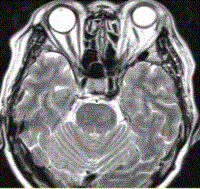

问题 女性,62岁。外伤后左侧突眼。MRI显示如下图。 该病可能的诊断是

选项 A.海绵状血管瘤 B.发育性静脉畸形 C.AVM D.毛细血管扩张症 E.动脉瘤 F.左侧颈内动脉海绵窦瘘 G.moyamoya

答案 F